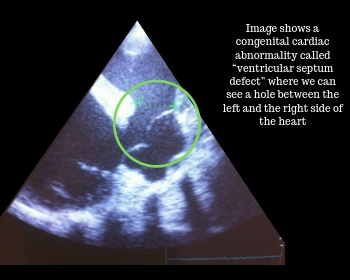

A good auscultation is the first step to detect cardiac diseases. Frequently “murmurs” can be heard between or superimposed to the normal heart beats. Some of them are innocuous and considered physiological, while others can be associated to valvular regurgitations or congenital defects. Based on auscultation we can suspect the origin of murmur, but further examination by means of an echocardiography is the only way to obtain a diagnosis and to see what the effect is on the heart.

Common alterations that we can observe during this examination are valvular regurgitations, which means that the cardiac valves don’t close well and allow some blood to leak back. This leakage can cause an abnormal noise during cardiac auscultation; we call this noise a “murmur”. Dependent on which valve is leaking and how severely it is leaking, this may or may not be a problem for the heart. Many horses will have valvular regurgitations without it causing a problem. However, over time, many of these will get worse and can start to impact the normal function and morphology of the heart and eventually also performance. Therefore, they need to be closely monitored.